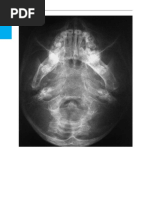

Image 1: Computed tomography, axial slices. oidal bulla; MM, middle meatus; MT, middle turb-

Ethmoidal bulla is seen on the right side and inate

retrobullar recess on the left side.